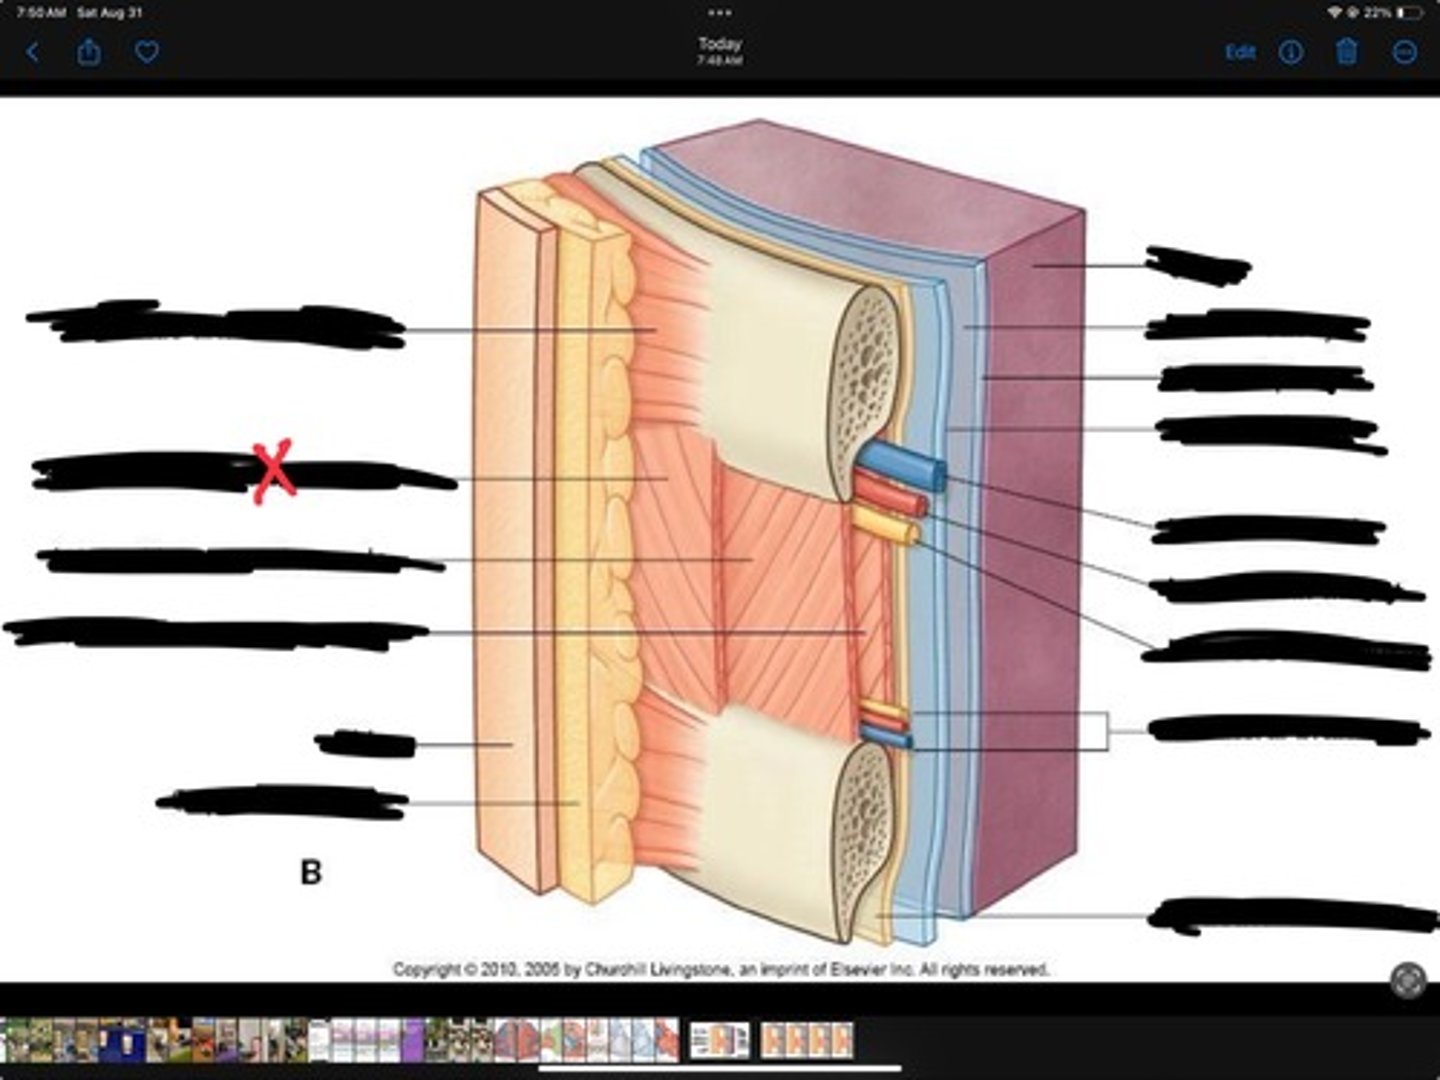

Innermost intercostal muscle

Skin

Internal intercostal muscle

External intercostal muscle

Serratus anterior muscle

Lung

Pleural cavity

Visceral pleura

Parietal cavity

Intercostal vein

Intercostal artery

Collateral branches

Intercostal nerve

Endothoracic fascia